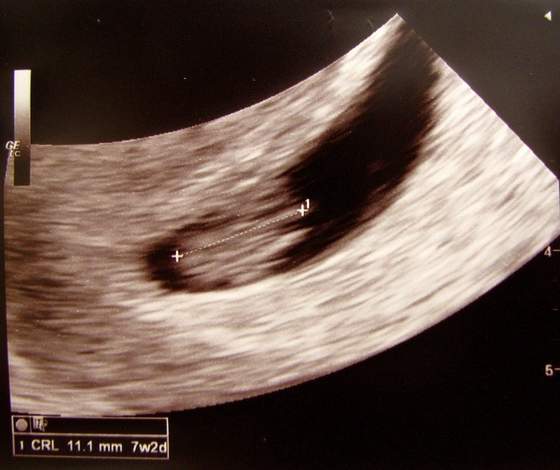

Witam Dziewczyny ja juz po wizycie karta już założonaserducho bije ok.171 uderzeń na minute. A maleństwo mam już 20.4mm wg usg 8tyg.6d a według OM 8tyg.4d mała rozbieżność termin porodu 13.01.2013. A stratuje z 59kg wagi:-)